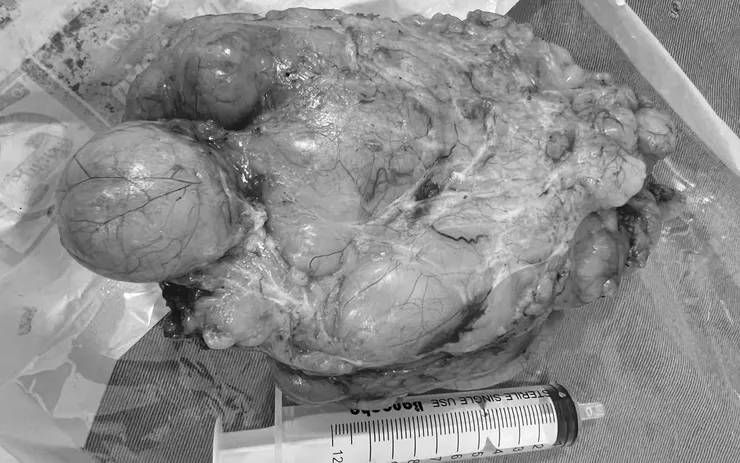

Sau hội chẩn liên khoa giữa các bác sĩ ngoại, gây mê hồi sức và hô hấp, ekip đã lựa chọn phương án an toàn tối đa. Ca phẫu thuật diễn ra trong hơn 1 giờ, các bác sĩ khéo léo bóc tách thành công khối u nặng gần 400 gram mà không gây tổn thương mạch máu hay dây thần kinh.

Sau mổ, bệnh nhân tỉnh táo, hô hấp ổn định, vết mổ khô, tiến triển tốt.